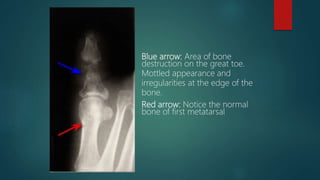

๏ต Plain films:

๏ต Low sensitivity early in the disease

๏ต 3-5 days: may detect soft tissue edema

๏ต 7-10 days: >66% still have normal x-rays

๏ต By 28 days, >90% of plain films will be positive

๏ต By the time there is X-ray evidence of bone destruction(30-

50% reduction of bone density), the patient has entered he

chronic phase of the disease

๏ต Characteristic finding: lytic lesions of cortical bone

destruction

๏ต Advanced disease: lytic lesions are surrounded by dense,

sclerotic bone, and sequestrum may be noted

Blue arrow: Area of bone

destruction on the great toe.

Mottled appearance and

irregularities at the edge of the

bone.

Red arrow: Notice the normal

bone of first metatarsal